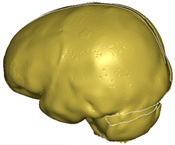

| Lamina interna | Giordano and Kleiven 2016; M. Ratajczak et al., 2019 [33,34] | 2.1 × 10−9 | 4 × 10+3 | 0.25000 | hexa 196,734 |  |

| Diploe | Giordano and Kleiven 2016; M. Ratajczak et al., 2019 [33,34] | 1.0 × 10−9 | 1 × 10+3 | 0.30000 | hexa 326,812 |  |

| Lamina externa | Giordano and Kleiven 2016; M. Ratajczak et al., 2019 [33,34] | 2.1 × 10−9 | 4 × 10+3 | 0.25000 | hexa 326,812 |  |